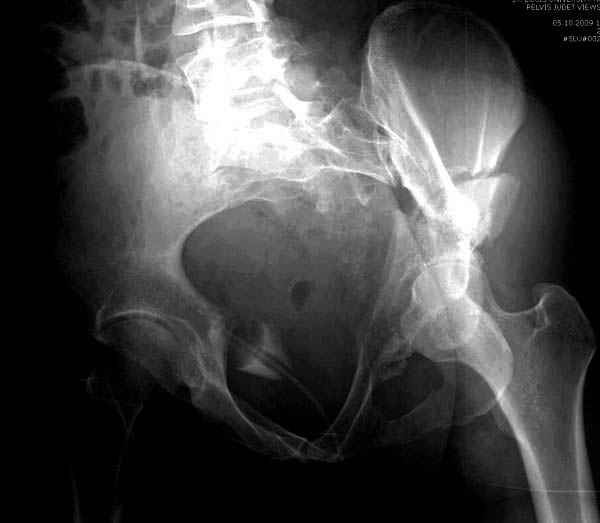

Все выступающие коллеги высказались насчет необходимости стандартных снимков по Judet, потому что для определения тактики лечения переломов вертлужной впадины 3Д снимки малоинформативны.

Летурнель разработал классификсацию на основании прямого, запирательного и подвздошного рентген снимков, котоые, кроме описания характера переломов, также подсказывают адекватный доступ для репозиции перелома.

Из того минимума, что представлено, мне кажется, мы имеем дело с двухколонным переломом вертлужной впадины. Обычно медиальный (центральный) "вывих" головки встречаются в сложных двухколонных переломах со смещением.

Здесь несколько вариантов двухколонных свежих переломов, которые были оперированы из одного-заднего, а также из двух: переднего и заднего доступов.